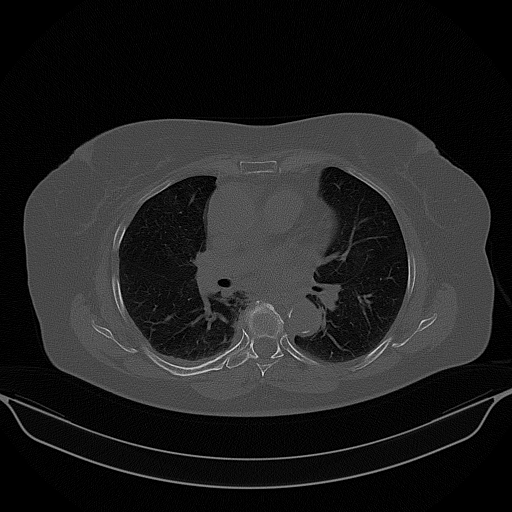

Original NATIVE CT scan (input)

Full window (WL 1023.5, WW 4095 β†’ Low βˆ’1024, High +3071)

Actual HU range: [-1024.0, 2210.0]